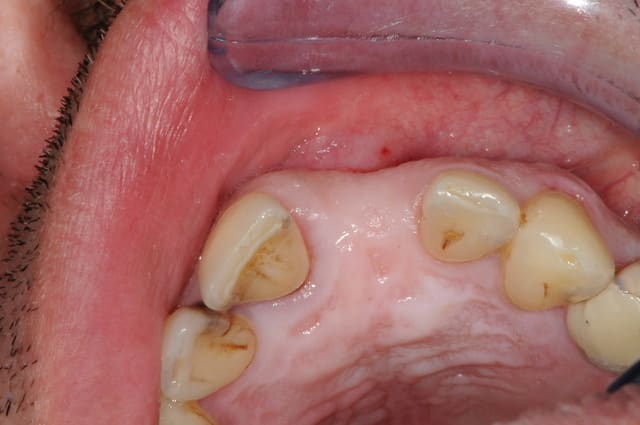

sinon, tu peux toujours partir d'un pilier standard et tu fait une provisoire dessus qui s'adapte au mieux...

comme olivier tu en sacrifies une vingtaine, mais bon, c'est pas grave tu peux t'en re-servir.